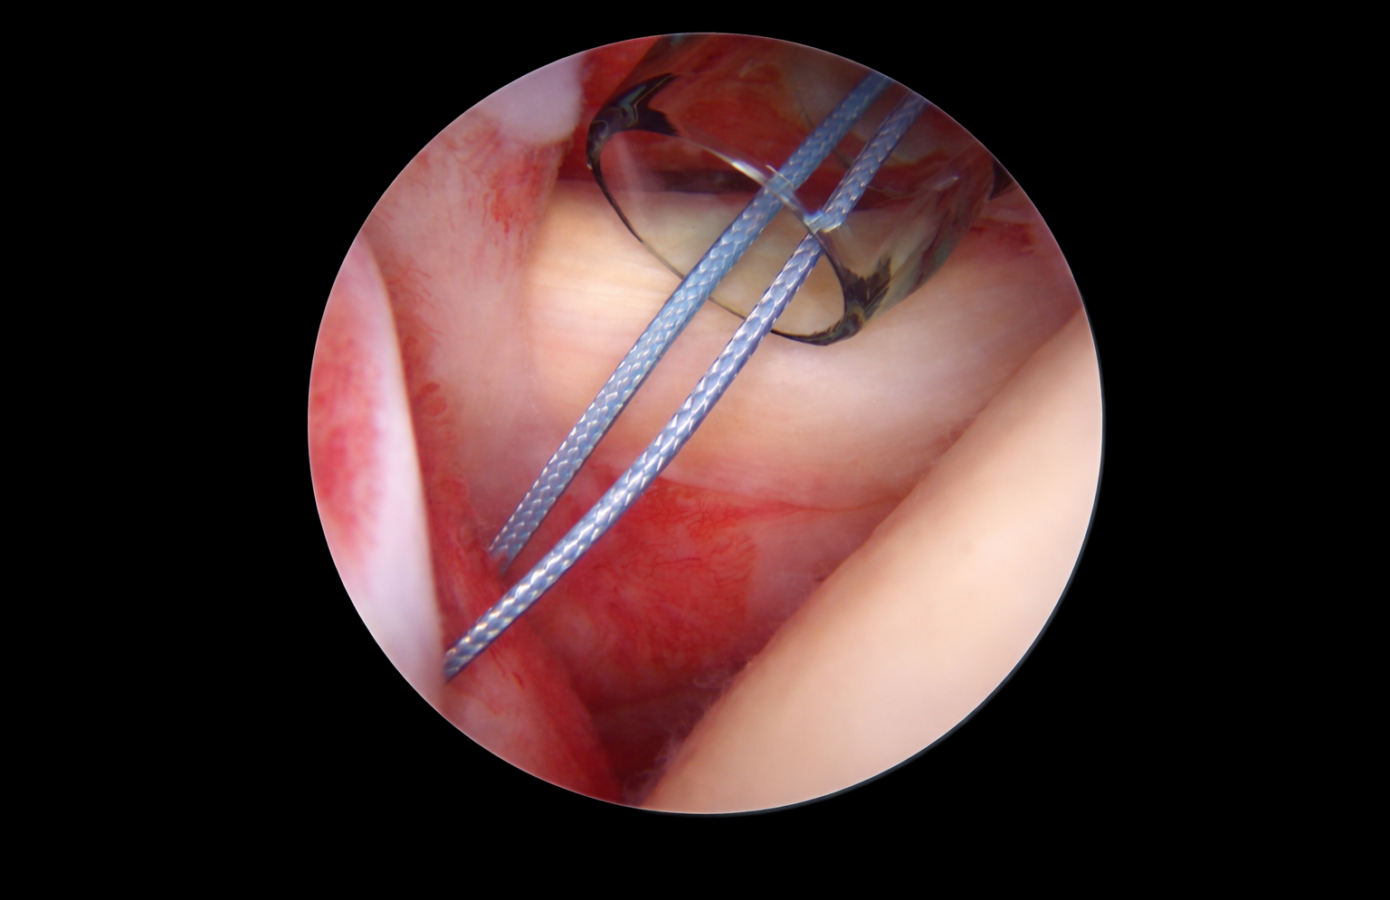

Biomaterials and Coatings

Biomaterials engineered for performance and compatibility

From polymer selection and degradation modeling to coating integration and textile compatibility, Corza Medical evaluates biomaterials within regulated production environments to ensure performance holds up from development through commercialization.

Coatings and surface engineering

Surface modifications engineered to enhance functionality while maintaining textile integrity and scalable manufacturability.

• Silicone for lubricity

• Wax for handling optimization

• Dyes for visibility

• Collagen for tissue interaction